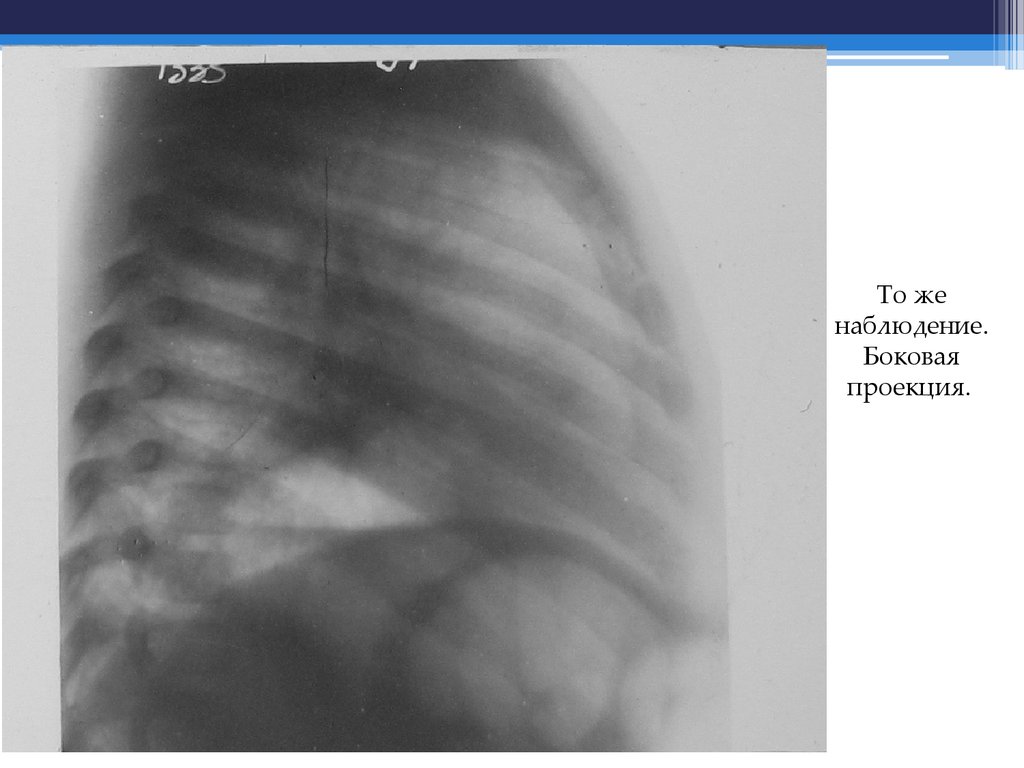

Острая первичная правосторонняя верхнедолевая пневмония,

осложненная мультицентрической формой абсцедирования.

То же наблюдение. На томограмме на фоне затемнения

многочисленные, разнокалиберные участки просветления.